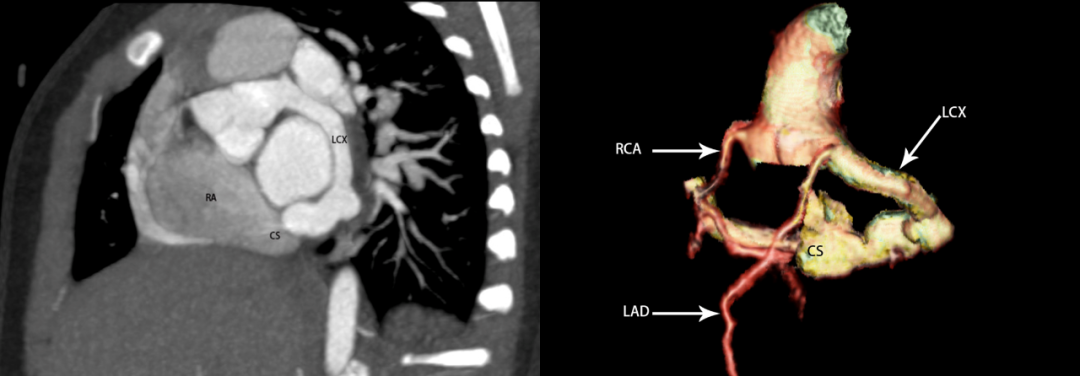

冠脉CT

心脏彩超:LV 25 mm,LA 18 mm,RV 11 mm,RA 20 mm;EF 70%,FS 38%。左冠状动脉开口增粗,内径约7 mm,走行迂曲,回旋支增粗,瘘入冠状静脉窦,瘘口径约6 mm,瘘口处频谱呈双期湍流,Vmax=1.6 m/s;冠状静脉窦明显增粗,内径约10 mm,其右房开口径约5.7 mm,频谱呈双期高速湍流,Vmax=5.4 m/s。